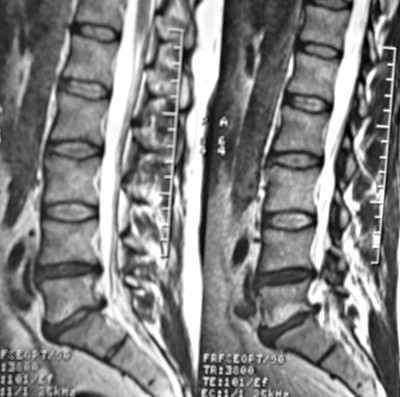

Questa condizione viene indicata al riguardo della colonna vertebrale.![]() |

![]() |

Indicano l'avvicinamento di due corpi vertebrali per degenerazione del disco vertebrale, che diventa più sottile.

Conflitti recidivanti di inadeguatezza a sopportare il carico, sentirsi schiacciati.